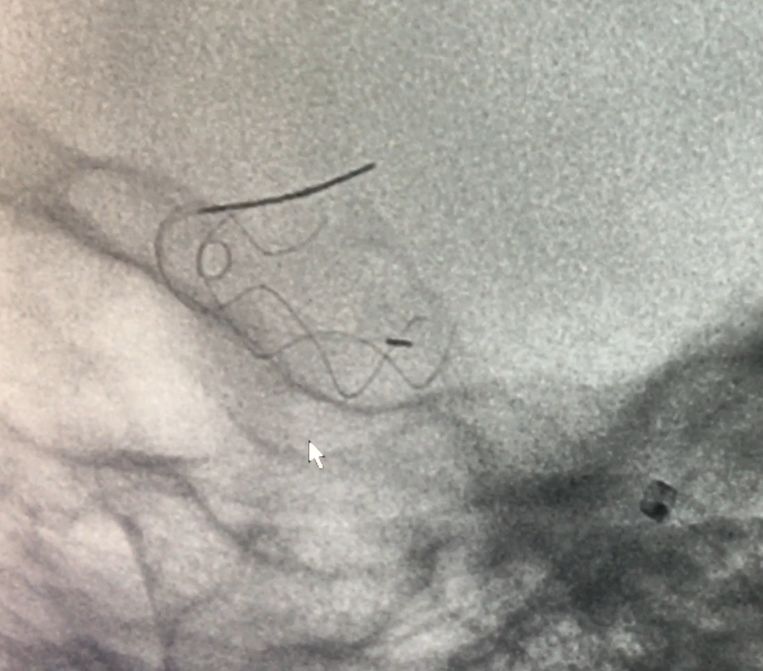

麻醉成功后,患者仰卧,常规消毒,铺巾, Seldinger法穿刺右侧股动脉,置入5F动脉鞘,置入5F造影管行右侧颈内动脉正侧位及3D造影后,更换6F长动脉鞘,6F中间导管在导丝引导下进入右侧颈动脉分叉端并固定。根据3D造影选择工作体位并放大做路图后,T-track微导管在微导丝引导下进入右侧大脑中动脉,经微导管送入4.0×45mm Tubridge®支架,观察 Marker位置后,于颈动脉分叉附近缓慢释放支架。

Tubridge®释放过程

锚定后,整体回撤至合适位置后,通过张力释放法缓慢释放支架,直至支架完全打开。观察见支架贴壁良好,动脉瘤颈完全覆盖,遂完全释放支架。

全脑DSA正侧位造影示血流通畅。

动脉瘤内造影剂滞留,未填弹簧圈。行Xper CT,观察见支架完全打开,贴壁良好。术程顺利结束。